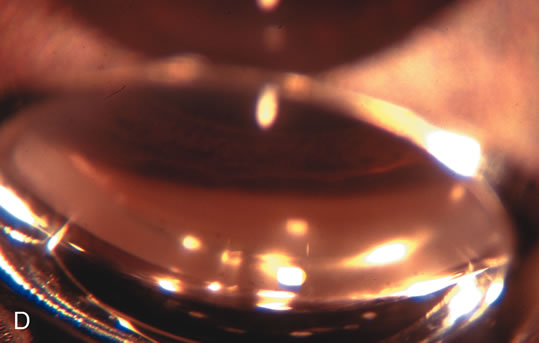

Nonpenetrating procedures as they exist today generally decrease postoperative complications but do not reduce IOP as successfully as trabeculectomy.140 The success rate also appears to be highly dependent on race, length of topical antiglaucoma therapy, and prior ocular surgery.141,142 Deep sclerectomy combined with phacoemulsification results in an IOP reduction similar to phacotrabeculectomy at one year with comparable visual outcome.143 Phacoviscocanalostomy lowers IOP by approximately 33%144 through either a one- or two-site approach145 (Fig. 4). Nonpenetrating procedures are in evolution, and their place in long-term glaucoma care is still unclear.

Fig. 4. Viscocanalostomy with deep sclerectomy and phacoemulsification. Nonpenetrating filtration procedures (NPFS) may be combined with phacoemulsification. Patients with mild disc damage and a history of limited topical drug therapy are the best candidates. Patients who require an IOP in the low teens are not good candidates for NPFS. By definition, NPFS is designed to lower IOP without penetrating into the anterior chamber, thereby avoiding the complications associated with trabeculectomy. Viscocanalostomy is intended to allow aqueous to percolate through a trabeculodescemetic membrane into a subscleral cavern created by the deep sclerectomy. The aqueous diffuses from the cavern into the dilated ostia of Schlemm's canal and into the episcleral venous plexus. A. Fashion a uniform 300-micron superficial scleral flap 1 mm into clear cornea. B. Construct a second 600-micron deep flap that facilitates the unroofing of Schlemm's canal, seen as the darker area. C. Use viscoelastic to dilate the ostia of Schlemm's canal. The major problem with viscocanalostomy is the eventual closure of the ostium decreasing flow to the episcleral plexus. D. Dissect the deep flap anteriorly into clear cornea creating the trabeculodescemetic membrane. This membrane is clearly seen between the scleral spur and the bend of the deep flap. The integrity of this membrane ensures the nonpenetrating portion of the surgery. Another problem with NPFS is the eventual fibrosis of this initially transparent membrane requiring goniopuncture. E. Deep sclerectomy gets its name from removal of the deep flap. Removal of this flap creates the potential subscleral space for accumulation of aqueous before it enters Schlemm's canal and exits the episcleral venous plexus. After removal of the deep flap, the superficial flap is sutured into place and conjunctiva closed. Approximately half of these procedures develop a shallow bleb.